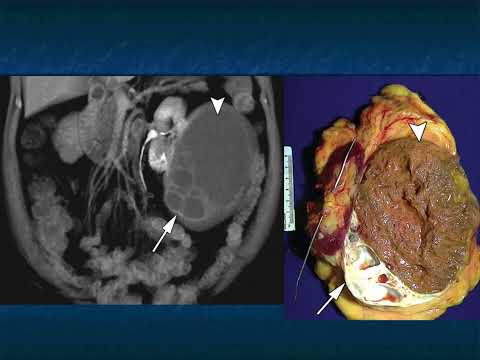

Access over 317,000 澳洲幸运5开奖官网开奖 Scans and the diagnosis that is identified for each case. The case studies range from 澳洲幸运5开奖官网开奖 Scans, MRI, and X-Rays, and are organized by anatomical region: Cardiac, Pancreas, Pediatric, Vascular, Gastrointestinal and more.